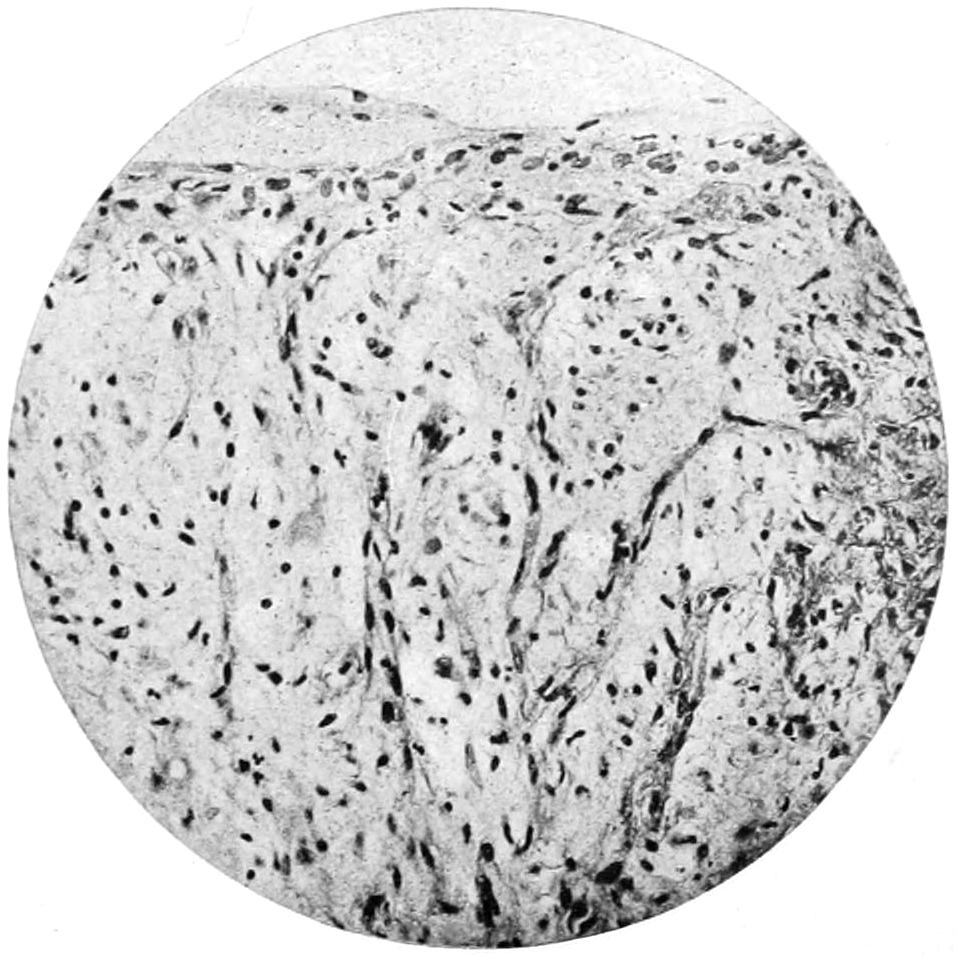

The value of a careful blood examination is well illustrated by Plate I, prepared by Dr. Irving P. Lyon, in which are displayed the alterations of greatest interest to the surgeon.